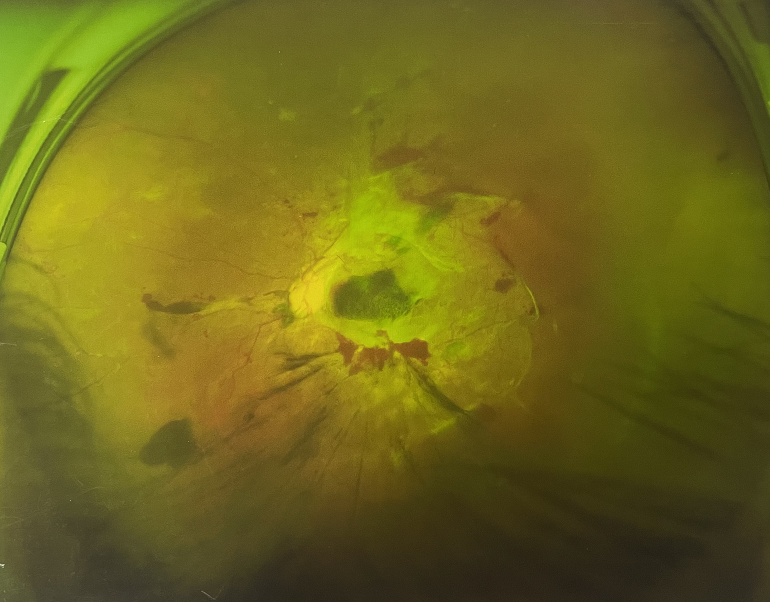

眼底出血一般多久能好?眼底出血可以由眼科本身疾病引起,常見(jiàn)的是視網(wǎng)膜靜脈阻塞、糖尿病視網(wǎng)膜病變、中心性滲出性視網(wǎng)膜病變、視網(wǎng)膜動(dòng)脈硬化、老年性黃斑病變、視網(wǎng)膜靜脈周圍炎。

另外,眼底出血還可以由全身疾病引起,比如糖尿病可以引起眼底出血,高血壓也會(huì)引起眼底出血,還有嚴(yán)重的腎病,血液方面的疾病都可以導(dǎo)致眼底出血。

眼底出血一般多久能好?眼底出血如果是輕癥,時(shí)間較短的患者大約3-6個(gè)月可以恢復(fù),如果是重癥或者病程較長(zhǎng)的患者,可能要持續(xù)1年,甚至2年時(shí)間。

眼底出血一般多久能好?眼底出血是醫(yī)生用檢眼鏡才能看到,患者和其他人看不見(jiàn)。眼底出血不是單獨(dú)的病,一般來(lái)說(shuō)是由眼科本身疾病造成,還可以由全身疾病造成。比如常見(jiàn)的視網(wǎng)膜靜脈阻塞、糖尿病視網(wǎng)膜病變等引起的眼底出血較常見(jiàn)。眼底出血一般多久能好?所以眼底出血的出血吸收時(shí)間也不一樣,要根據(jù)病情輕重決定其預(yù)后,出血吸收時(shí)間也不一樣。